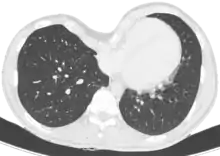

Aspect radiologique d'une barre de Nuss en post-opératoire. À noter qu'une scoliose est associée au pectus excavatum.

La technique chirurgicale mini-invasive de Nuss, plus récente[16], consiste à introduire une ou deux barres à l'intérieur de la cage thoracique du patient et à les maintenir à l'aide de stabilisateurs, le tout sous contrôle thoracoscopique. Cette intervention est privilégiée pour les jeunes personnes n'ayant pas fini leur croissance (idéalement vers 15 ans, pour une ablation des barres à 18 ans, âge de fin de croissance) et possédant donc encore une structure de cage thoracique relativement souple. L'opération redresse instantanément le thorax mais empêche la pratique de sport pour un délai de 3 mois et interdit les sports de contact (rugby, karaté…) pendant toute la durée durant laquelle le patient porte la ou les barres. Cette technique nécessite une durée d'hospitalisation d'une semaine dont 4 à 5 jours sous péridurale. Plus cette opération est pratiquée tôt, moins les douleurs physiques sont grandes (croissance des cartilages). Le matériel est généralement enlevé trois années après avoir été mis en place, une fois que la structure osseuse est solidifiée (transformation des cartilages osseux en os solides, due à l'âge). Le rapport risques/bénéfices de la technique de Nuss est cependant remis en cause du fait de la gravité des complications médicales qui peuvent résulter d'un déplacement de la barre (notamment des perforations cardiaques ou des interruptions de la veine cave)[17].